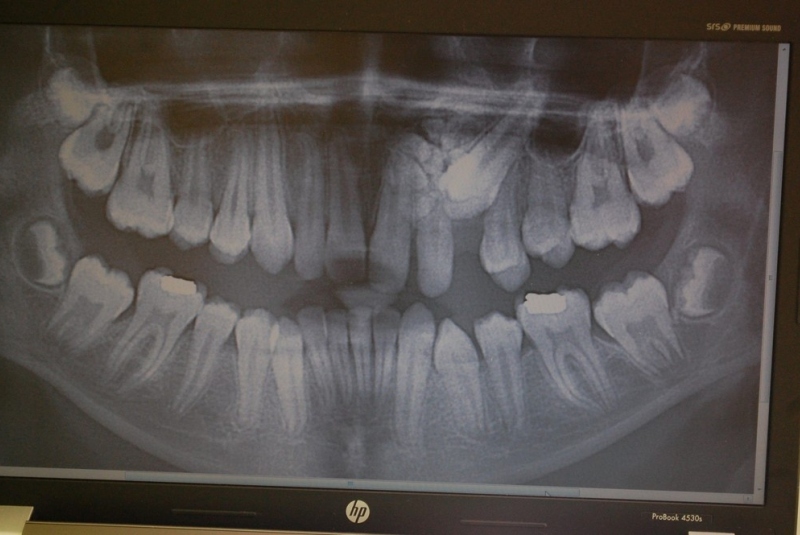

- Implantológia:

1. nadstavba kosti augmentačnými materiálmi (umelé kostné tkanivo, sinus lift a pod.)

2. implantológia, vrátane 3D - dentálneho CT